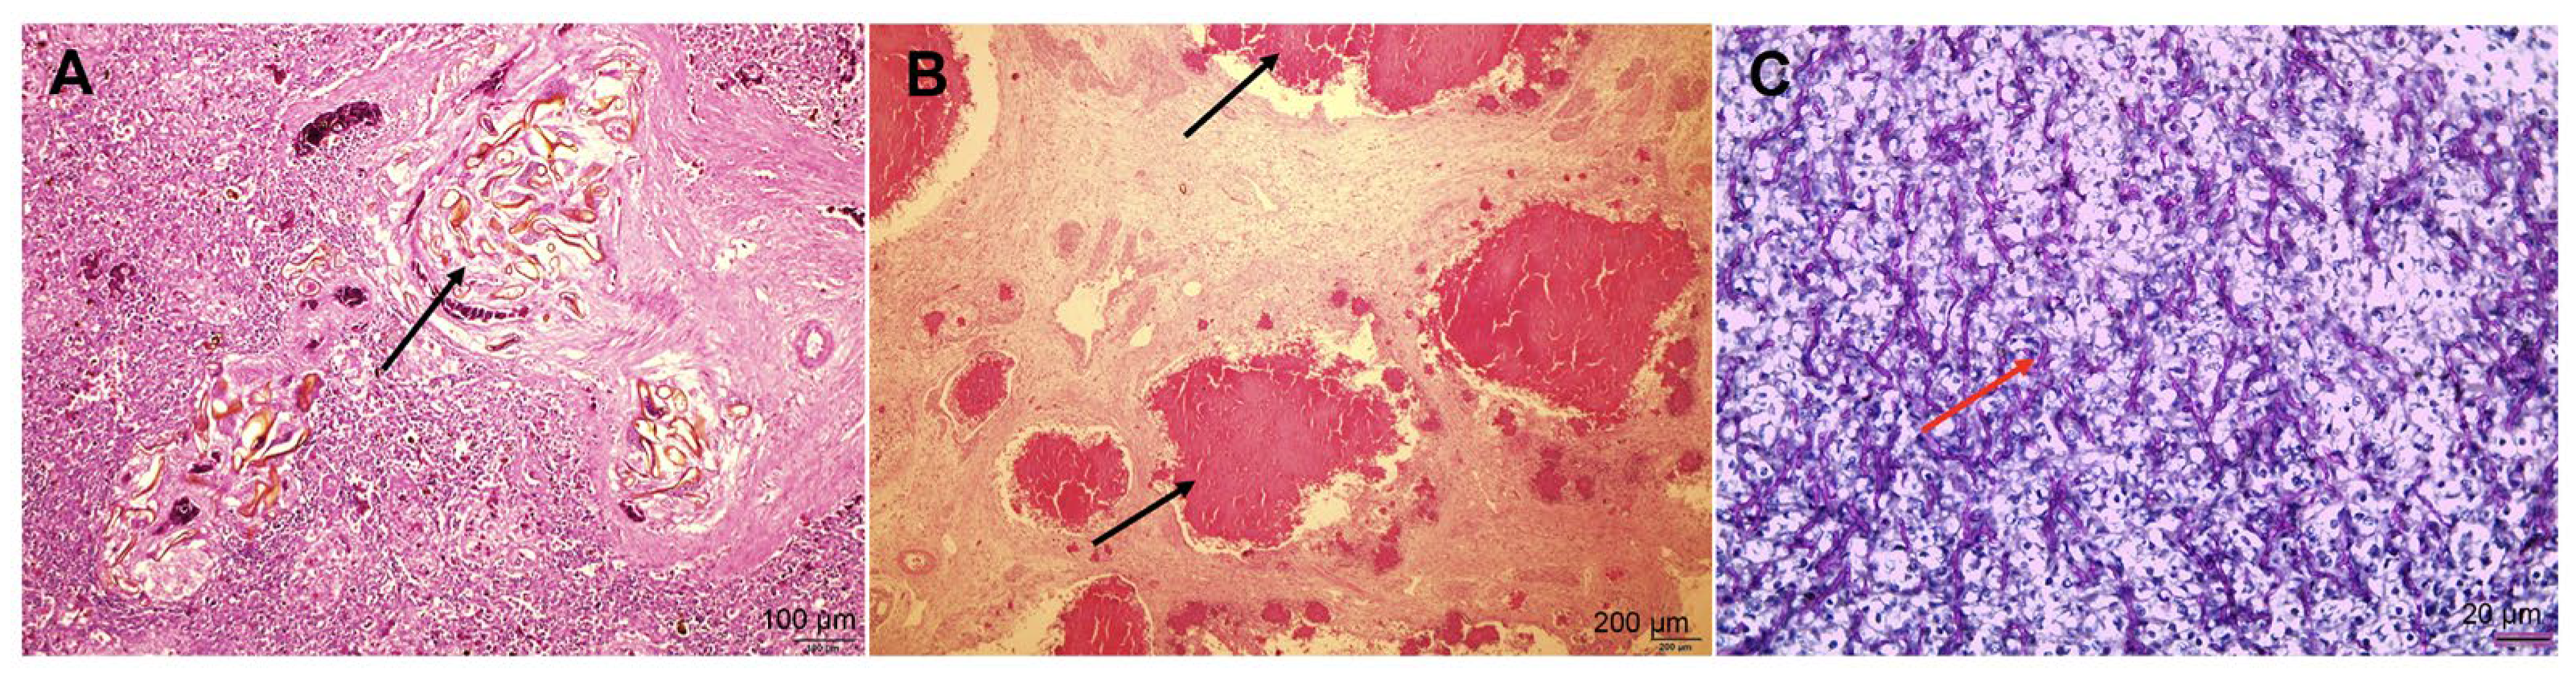

3.2.2. Histopathological Findings